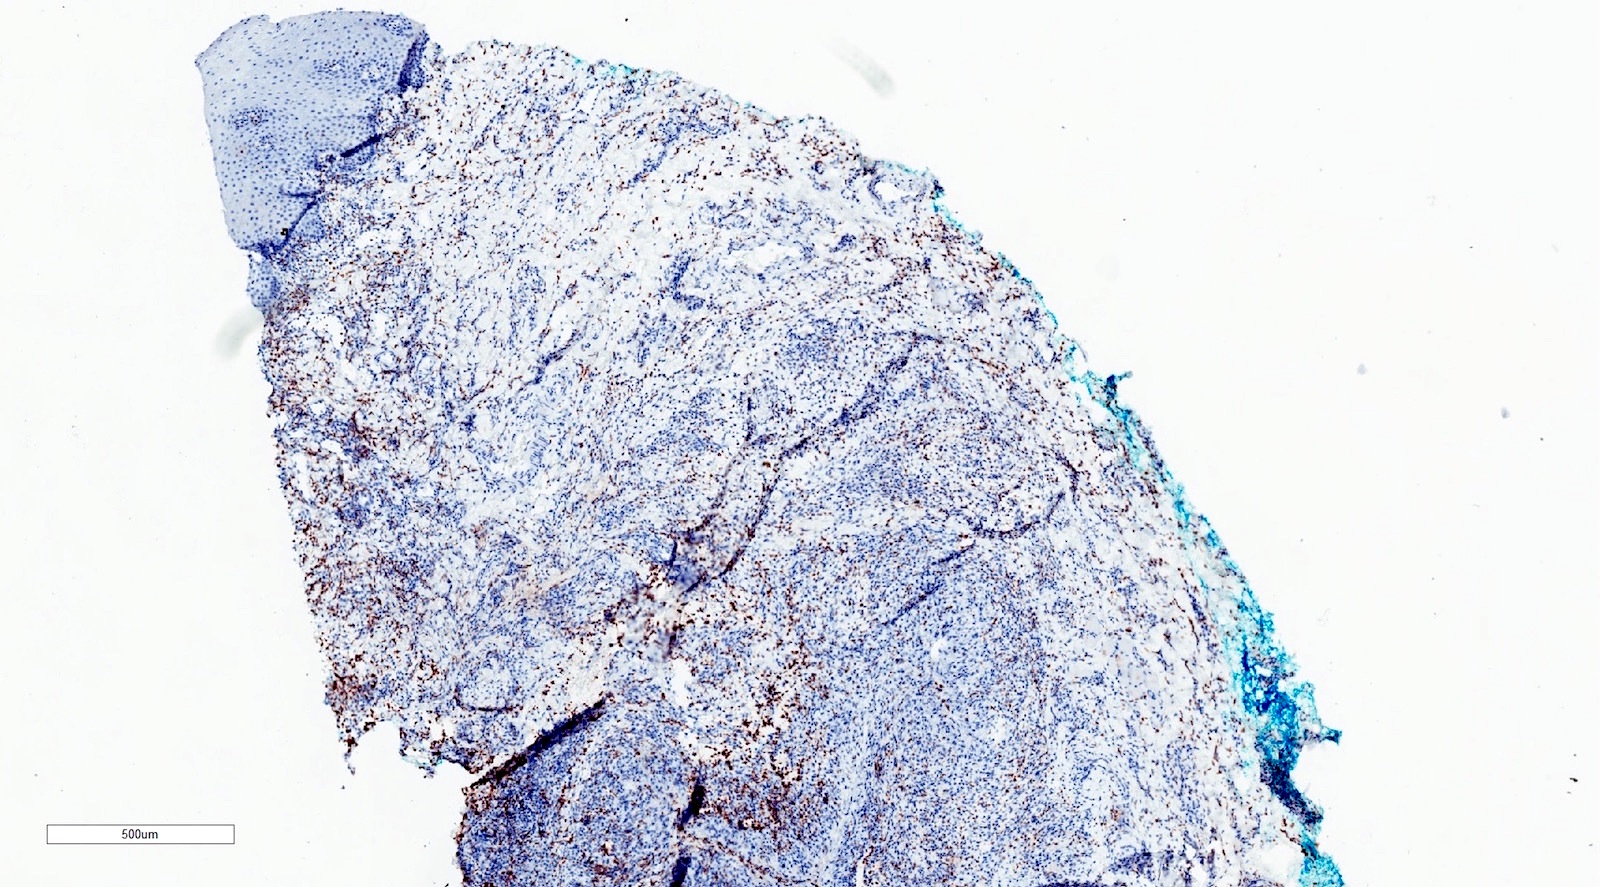

Microscopic (histologic) images

Positive stains

- Note: stains typically not needed to make the diagnosis

- CD68

- PAS-D

- Mucicarmine

- Alcian blue